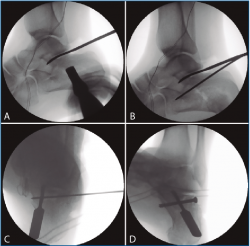

Figura 4. A: control de escopia intraoperatoria (perfil) de la lesión reducida con ayuda de periostotomos; B: control de escopia intraoperatoria (perfil) tras insertar la primera aguja mientras se mantiene la reducción con un periostotomo; C: control de escopia intraoperatoria (axial de calcáneo) tras insertar la primera aguja mientras se mantiene la reducción con un periostotomo; D: control de escopia intraoperatoria (axial de calcáneo) tras colocación del primer tornillo de osteosíntesis.